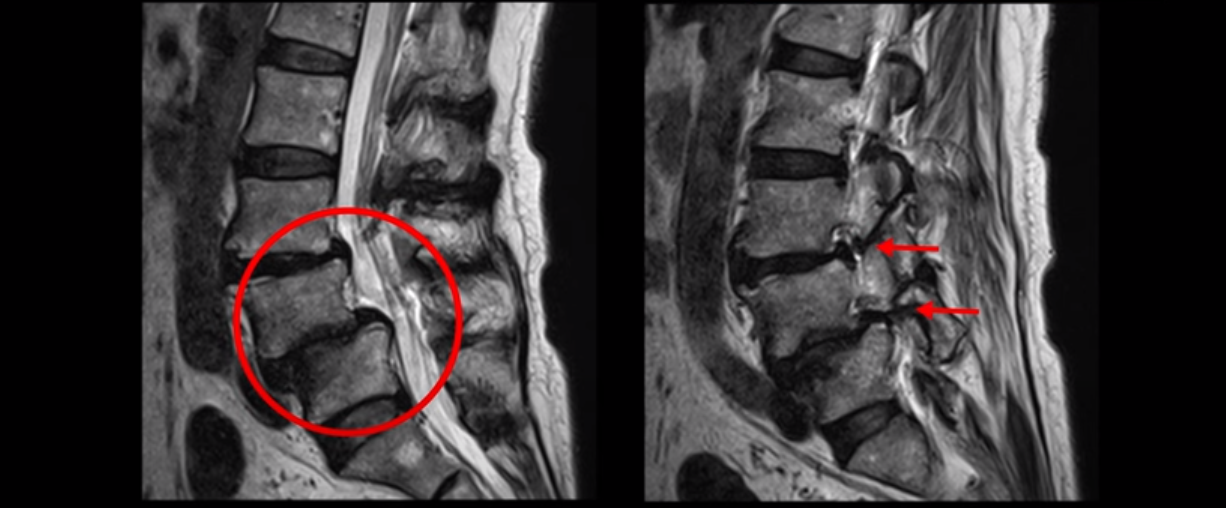

이분 또한 전방전위가 2단계로 매우 심하고, 신경 구멍도 두 마디가 좁아져 있습니다.

전방전위와 협착이 다 심하니까 대학병원에서 나사 6개를 박는 유합술을 권유 받으셨습니다. 그런데 이분이 처음 아프게 된 건 작년 10월인데, 이분이 만약 아프기 전인 작년 초에 MRI를 찍었다면 지금의 MRI와 많이 다를까요? 아닙니다. 거의 차이가 없을 겁니다. 작년 10월에 무리한 일과 운동 때문에 허리 근육에 문제가 생기면서 신경이 눌리기 시작한 겁니다. 만일 아프지 않을 때 MRI를 찍고 신경이 눌렸다고 나사 박는 수술을 하자고 하면, 어떤 사람이 수술을 받을까요?